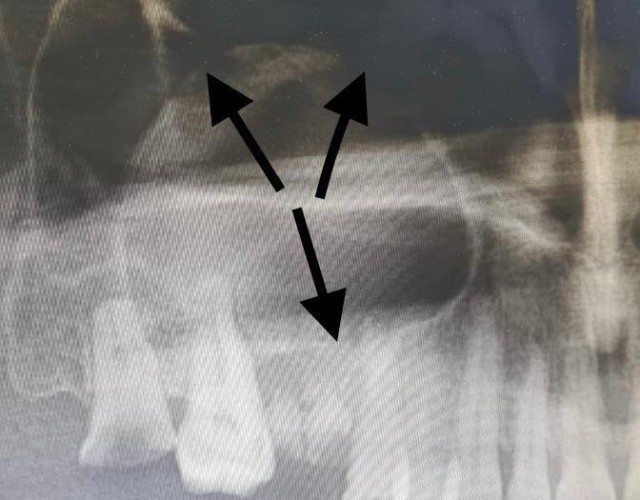

نجح – بفضل الله – فريق طبي في مستشفى القريات العام، في إستئصال ورم بالفك العلوي لمريض ، حيث تبين بعد إجراء الفحوصات الطبية اللازمة، وجود ورم في الفك العلوي ممتد إلى الجيوب الأنفية وصولاً إلى العين .

وقد تقرر إجراء تدخل جراحي ،حيث نجح فريق طبي متكامل من جراحة الوجه والفكين – بتوفيق من الله – في إستئصال الورم، وقد تحسنت حالة المريض بعد العملية، ويتمتع حالياً بصحة جيدة بحمد الله.